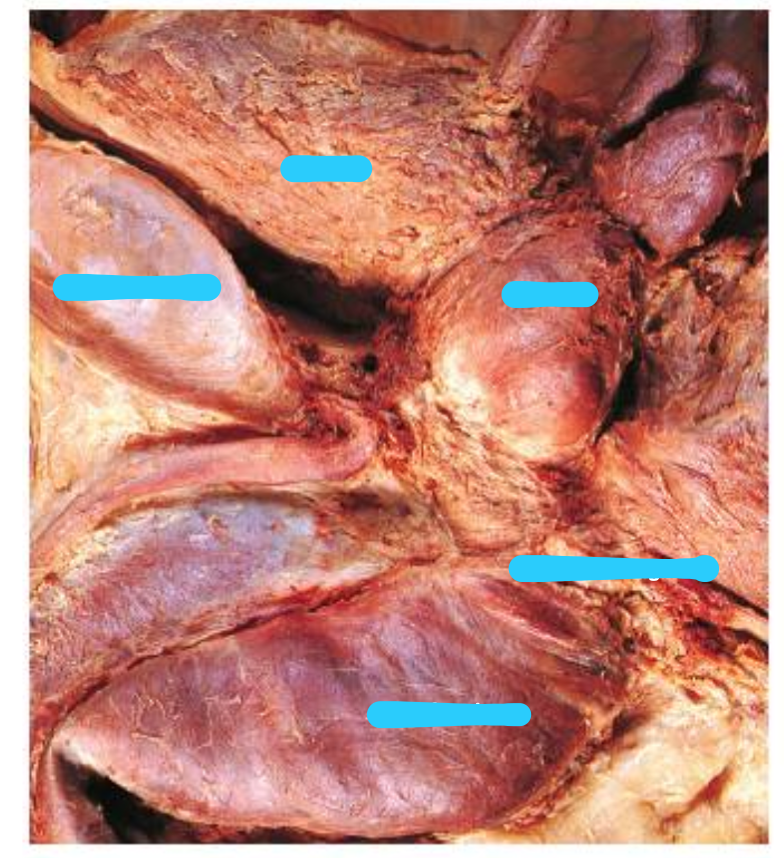

Name the vesicles (blue) and structure (green)